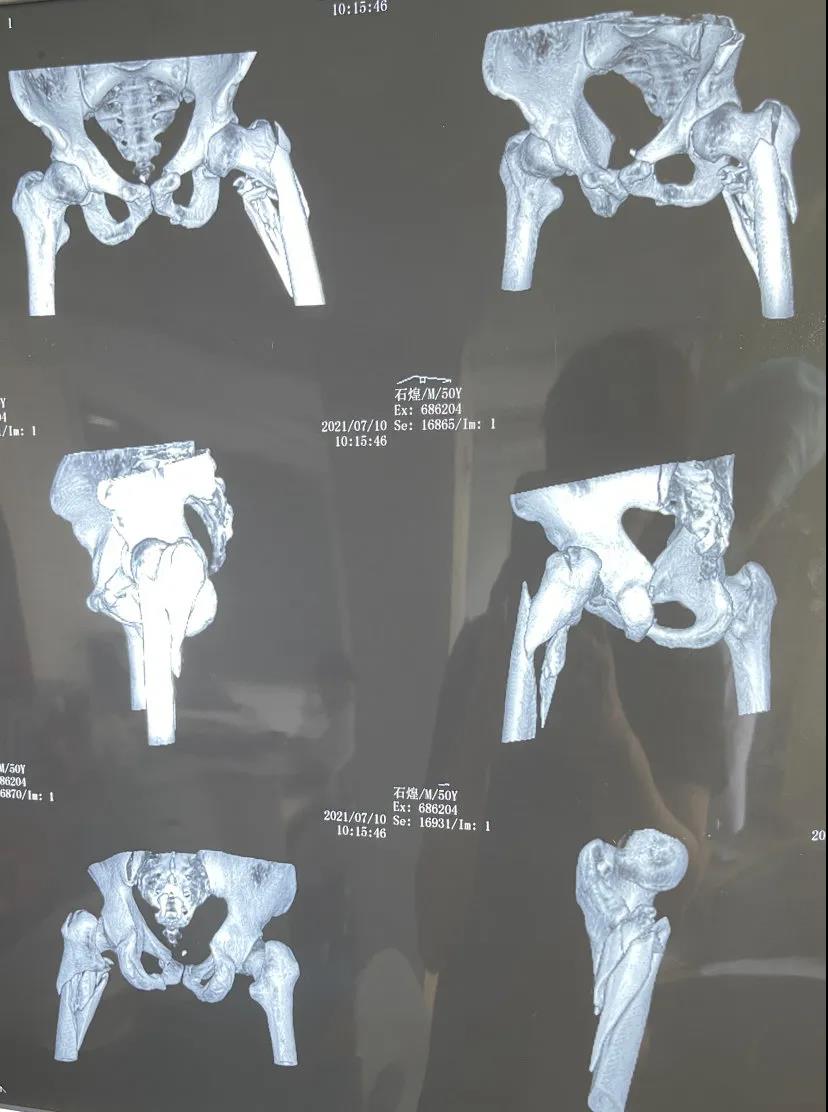

▲术前影像学资料

7月18日,石某在户外高空作业,不慎坠落,由120急救车送入万丰医院急诊抢救室。当时,患者神志不清,意识淡薄,头面部、胸腹部、髋部、左侧上下肢、口腔、鼻腔等多处出血,咬合关系紊乱,不能言语。影像学检查显示,病人不仅骨盆、下颌骨、左趾骨、左跟骨、腰椎、鼻骨等多处骨折,还伴有左上肺感染性病灶,双上肺肺大泡,病情危重,石某老婆得知病情这么重,心急如焚,几度哽咽。